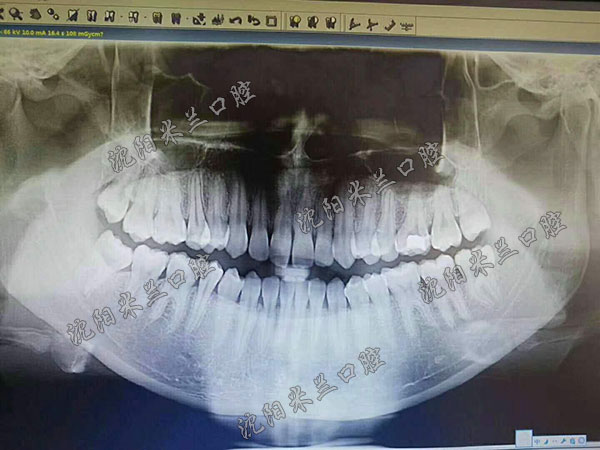

< 全景牙齿片 >